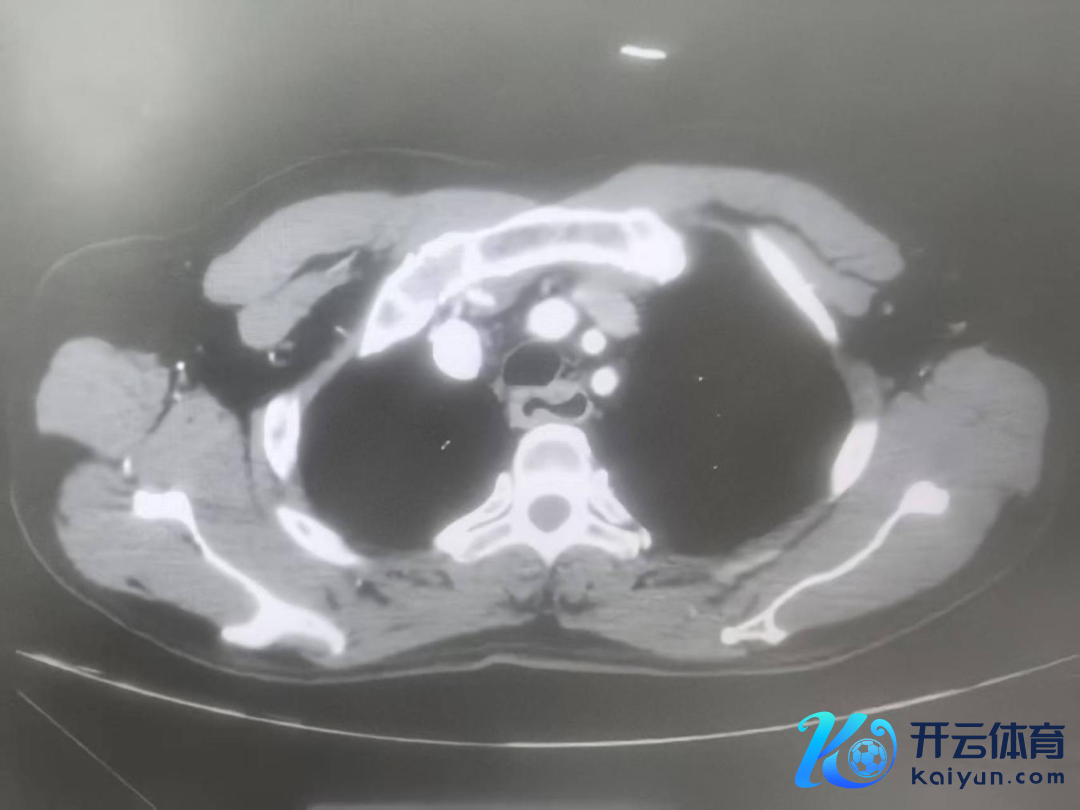

心怀外科副主任、主任医师王理智,主治医师刘炬博士团队接到诊断后,为陈阿公进行全面查验。胃镜领导:肿瘤位于食管启齿处,厚11mm,冲破食管外层,仍是环绕食管3/4周,周围多发肿大淋献媚;CT领导:食管高位肿瘤,48mm*18mm*16mm,与支气管后壁分界不清,周围多发淋献媚;PET-CT领导:2-4胸椎水平食管上段食管癌,右下颈气管旁、右上气管旁淋献媚疑退换。抽象计划局部晚期、高位、食管恶性肿瘤,径直进行手术的风险及难度齐很大,大夫提倡实验新扶助调养后再进行手术。但这样的调养形状,让家属们堕入两难境地。

△查验效能